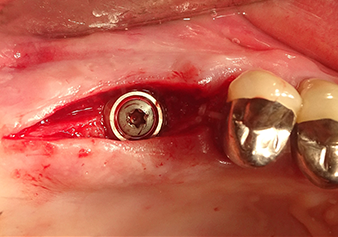

Lo strumento I2A (diametro 2,0 mm) è stato quindi impiegato per perforare il pavimento sinusale in modo graduale e su superfici molto ridotte. Tale metodo piezochirurgico previene il danneggiamento della membrana di Schneider. Durante l'utilizzo di Z25P, la membrana risultava già essere leggermente sollevata dal fluido di raffreddamento fornito attraverso la punta dello strumento (Fig. 3). La quantità di fluido di raffreddamento presente era solo del 50% per evitare che la sede dell'impianto registrasse un'elevata pressione.